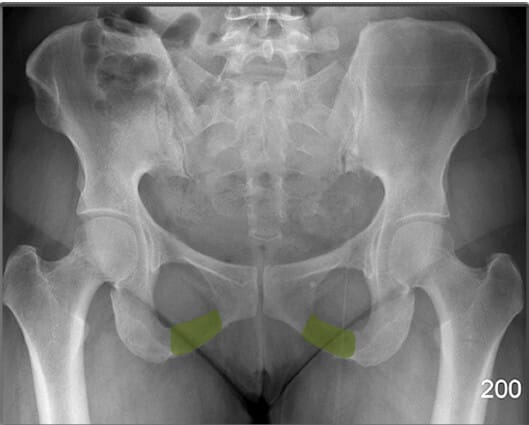

소전자 (Lesser Trochanter)

| 소전자 (Lesser Trochanter) |

| ✅ 대퇴골의 후내측에 위치한 작은 돌기이며, AP view에서는 보통 대퇴골 내측에서 작고 조밀한 음영으로 관찰됩니다. |

| 🔴 굴곡근(Hip Flexor)의 부착점이며, 과사용성 견열 손상이 발생할 수 있습니다. |